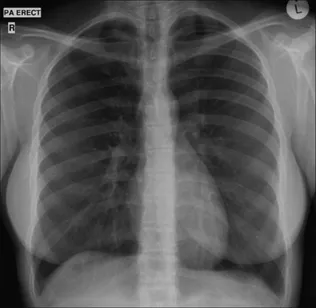

Figure 1.1 Normal PA CXR. Standard radiographic technique allows comparison of the heart size on any previous or subsequent PA CXR.